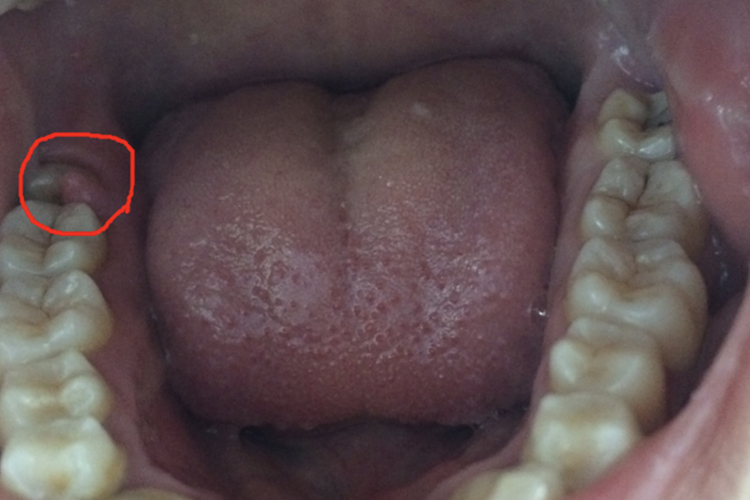

牙息肉在临床上一般指牙龈息肉,为肉芽样增生体,息肉蒂源自邻间牙乳头。

牙龈息肉多与牙龋洞和食物长期嵌塞有关,持续不良刺激可导致牙龈增生,形成息肉。

牙息肉在临床上一般指牙龈息肉,息肉为肉芽样增生体,体积可大可小,息肉蒂源自邻间牙龈乳头,一般无自发痛,可在进食时出现疼痛或进食出血现象,不敢用患侧咀嚼食物。

牙龈息肉多是在患牙邻面出现龋洞时,由于食物长期嵌塞加之患牙龋损处粗糙边缘的刺激, 牙龈乳头向龋洞所形成的空间增生,形成息肉样肉芽组织,导致牙龈息肉。